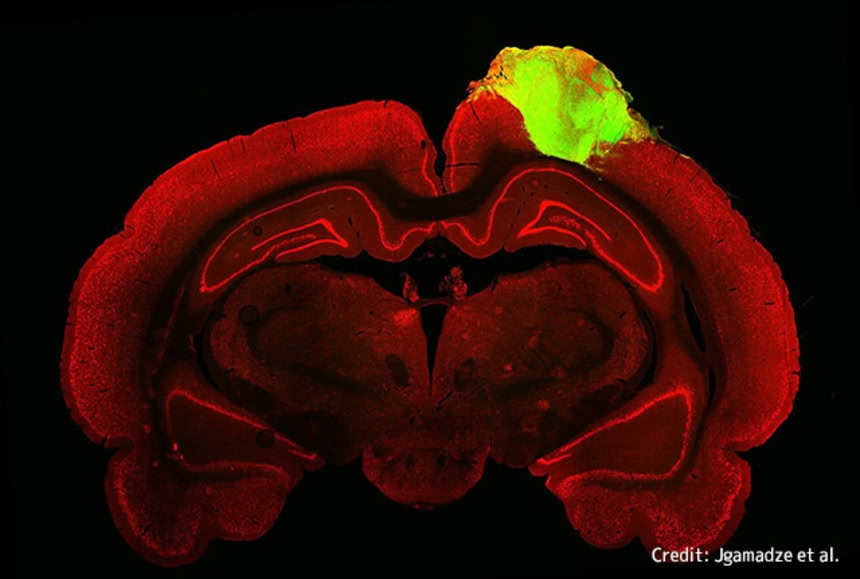

続きを読む生きているラットの脳に、人間の幹細胞から培養したミニ脳(ヒト脳オルガノイド)を移植したところ、見事に一体化したそうだ…

続きを読むなにやらマッドサイエンスじみているがこれも医学発展の為だという…